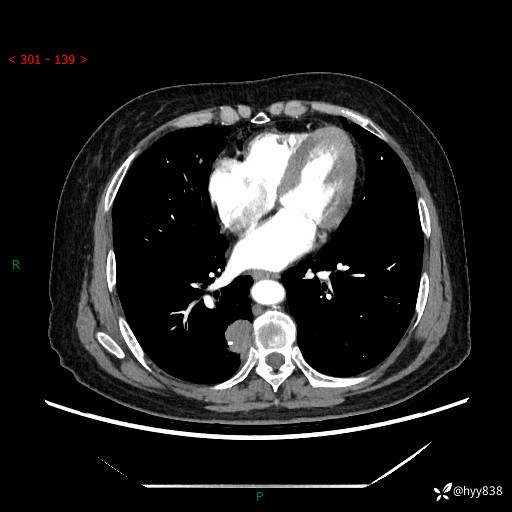

增强动脉期+静脉期

两期CT值:55Hu 53hu